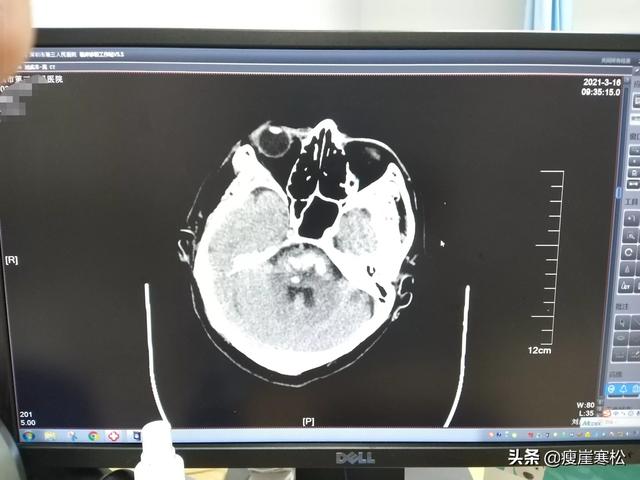

1. maux de tête intenses, vertiges, vomissements, suivis de troubles de la conscience. Un chauffeur de 38 ans, après avoir été pris de vertiges et de vomissements, a livré des marchandises pendant deux heures avant d'appeler un ami pour qu'il l'emmène à l'hôpital, puis il est tombé dans le coma et a subi un infarctus cérébral.

Sans aucune connaissance médicale, j'ai commis l'erreur d'essayer de me sauver avant que mon infarctus cérébral n'envoie un signal de détresse

Peut-être est-ce la miséricorde et la faveur de Dieu à mon égard. Un à un, j'ai commencé à me sauver avant le début de l'infarctus cérébral par erreur, mais je n'ai moi-même que peu de connaissances médicales. Lorsque j'ai pris conscience du danger que représentent les maladies cardiovasculaires pour la vie des gens, j'ai éprouvé une profonde gratitude, mais aussi un soupçon de panique et de peur. En fait, avant qu'un infarctus cérébral ne se produise, le corps de chacun envoie des signaux de détresse, mais nous n'y prêtons pas attention, ce qui favorise l'évolution de l'infarctus cérébral vers l'accident vasculaire cérébral. J'ai 44 ans cette année, à cause d'une prostatite chronique qui a entraîné une insuffisance rénale et des douleurs dorsales, qui se sont ensuite transformées en vertiges et en gonflements, en insomnies, en rêves ...... et parfois en légers maux de tête. À l'époque, je n'avais pas remarqué que l'athérosclérose me touchait, y compris le traitement de la prostate. Les médecins de l'époque ne pensaient pas non plus que je serais atteint d'une maladie vasculaire cardio-cérébrale à un jeune âge, ils m'ont simplement demandé d'arrêter de fumer, de boire de l'alcool, de manger des piments et des fruits de mer et de faire plus d'exercice, alors j'essaie de fumer et de boire moins, de manger moins épicé, tant que j'ai du temps libre, je reste à la maison pour pratiquer la boxe et faire des pompes, etc. Lorsque j'ai eu 30 ans, j'ai soudainement constaté que le côté de mes cuisses en marchant avec du poids se déchire souvent et que l'athérosclérose entraîne l'occlusion de petits vaisseaux sanguins, l'ischémie est également connue sous le nom de vascularite, mais je n'y ai jamais pensé et je n'y ai jamais prêté attention, parce que je vis à la campagne, je laboure, je coupe du bois, je plante et je fais d'autres travaux physiques, je ne pensais pas que le travail physique pouvait accélérer la circulation sanguine et atténuer la maladie, mais je pensais seulement qu'à la campagne, il y a toujours un travail sans fin à faire. J'avais simplement l'impression qu'il y avait toujours une infinité de choses à faire à la campagne. Par conséquent, je n'ai pas prêté attention à mes symptômes et je ne me suis pas fait examiner. À l'âge de 35 ans, j'ai commencé à avoir des maux de tête, et je ne connaissais toujours pas ces maladies, mais lorsque j'avais des vertiges et des douleurs, je faisais de l'exercice ou je jouais au basket-ball, puis je me mettais debout sur la tête, et je me sentais beaucoup plus détendue après avoir fait ces exercices. Plus tard, les champs du village ont été exploités, et il n'y avait rien à faire à la maison, je faisais moins d'exercice, je dormais à la maison, et je ressentais souvent des engourdissements d'un côté de mon corps, mon poids atteignait 150 livres pour une taille de 1,65 cm, et une fois je me suis levé un peu plus longtemps et j'ai soudainement ressenti un engourdissement dans ma jambe droite que je n'avais jamais ressenti auparavant, et je ne savais pas qu'il s'agissait de signes précurseurs de l'apparition de maladies cardiovasculaires et vasculaires cérébrales. Je ne pensais pas que tout ce que je faisais atténuait invariablement le développement des maladies cardiovasculaires, et que l'engourdissement du sommeil était également bien meilleur. Plus tard, parce que la famille n'a pas planté, j'ai dû aller à l'usine pour travailler, pas quelques mois, j'aime regarder le téléphone portable pour devenir inactif. 18 ans d'un jour, soudainement l'œil droit ne peut pas voir les choses clairement, regarder les choses au milieu de l'œil il y a une ombre noire, la tête continue à faire mal, je suis allé à l'hôpital, le médecin a dit que c'était la rétinite, a prescrit beaucoup de médicaments d'activation du sang, y compris les capsules de thrombose composée, etc, plus je plus tard acheté leurs propres dizaines de boîtes de médicaments d'activation du sang. ......4 mois plus tard, mes yeux allaient beaucoup mieux et j'ai arrêté de prendre les médicaments. 19 ans, j'ai constaté que les objets que je tenais dans ma main tombaient parfois involontairement, que j'avais mal au cou lorsque je tournais la tête vers la gauche et que j'avais également mal à la tête. À ce moment-là, je me suis souvenu que la superstar du kung-fu Bruce Lee avait choisi de prendre de l'aspirine et des médicaments pour améliorer le sang, et je suis donc allé à la pharmacie pour acheter de l'aspirine et des médicaments pour améliorer le sang. En 2020, mon beau-père a été hospitalisé, je suis allée lui rendre visite à l'hôpital et, par coïncidence, j'ai parlé au médecin de mon mal de tête. Le médecin m'a conseillé de faire un scanner et une IRM (......). Lorsque le médecin a regardé mon rapport, il m'a dit : "Vous voulez prévenir les infarctus cérébraux, vous avez besoin d'une assistance médicale". Les personnes âgées de 40 ans et de 60 ans sont atteintes d'athérosclérose, de plaques au niveau du cou, de multiples foyers d'infarctus ischémiques sont stockés dans le cerveau. ...... Après avoir écouté les paroles du médecin, j'y ai cru à moitié. Pour savoir ce qu'il en était, j'ai pris le film et la liste pour trouver un autre médecin. Après avoir lu mon film, le médecin m'a dit que j'étais atteint d'une maladie cardiovasculaire, que le cerveau et les membres inférieurs présentaient de multiples foyers et plaques d'athérosclérose, que si l'on n'y prenait garde, il y aurait à tout moment un infarctus cérébral, qu'il m'avait demandé quand j'avais commencé à présenter ces symptômes et qu'il avait vérifié les trois points suivants : hypertension artérielle, hypercholestérolémie et hyperglycémie. Il m'a demandé quand j'ai commencé à avoir ce symptôme et a vérifié les trois taux élevés : hypertension, hypercholestérolémie, hyperglycémie. J'ai mis ces conditions et j'ai fait du sport actif, y compris manger des ecchymoses et des médicaments stimulant la circulation sanguine, et j'ai arrêté de fumer, de boire de l'alcool, de manger épicé, et le médecin a dit après que le médecin a souri et a dit : vous ah ...... est Dieu en votre faveur, laissez vous prendre par erreur de l'aspirine et faire de l'exercice actif et du sport, arrêter de fumer et de boire de l'alcool pour manger des médicaments stimulant la circulation sanguine. Prévenir le développement de l'infarctus cérébral, sinon vous auriez eu un accident vasculaire cérébral ...... De cette façon, je prends de l'aspirine tous les jours, des statines et d'autres médicaments anticoagulants activateurs de sang, mais de plus en plus de lignes d'ongles, de lignes d'ongles convexes et concaves au nom du corps souffrant de signes de maladies chroniques, et à cause de mon estomac n'est pas bon, inquiet de l'aspirine et d'autres médicaments occidentaux avec des effets secondaires, j'ai réfléchi à la recherche d'un autre type d'activateur de sang, et j'ai cherché un autre médicament pour activer le sang. Je cherchais un autre médicament pour activer la circulation sanguine et éliminer la plaque. Je prends maintenant ma propre médecine chinoise, j'ai l'impression que l'effet est meilleur que celui de l'aspirine, il n'y a pas d'effets secondaires, mais aussi en même temps pour réguler d'autres symptômes des organes du corps, et actuellement je sens que les ongles ont de moins en moins de bosses horizontales ...... J'espère que je peux devenir un cas d'inversion de l'infarctus cérébral, je suis maintenant dans l'usine du travail normal, chaque jour pour prendre leur propre médicament. Je ne sais pas s'il y a des netizens qui souffrent d'infarctus cérébral comme moi, et j'espère que vous pouvez activement le prévenir, l'infarctus cérébral est fatal, il y a des opinions différentes, vous pouvez communiquer dans la section des commentaires.